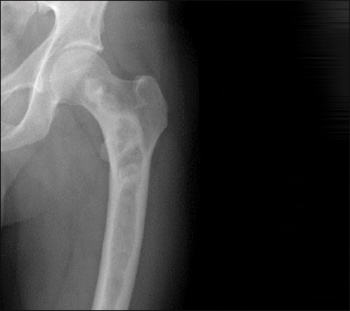

Diagnosis is usually made on clinical grounds, based on radiographic appearances and location. Areas of skeletal involvement are established early with 90% of craniofacial lesions evident by five years of age and 75% of all FD lesions established by 15 years of age. Although any area of the skeleton can be affected, common sites include the skull base and proximal femora. Skull base disease may result in facial asymmetry and, rarely, cranial nerve involvement. Femoral disease may present with a classic shepherd’s crook (coxa vara) deformity. Radiographically, these sites appear different. Craniofacial FD has a sclerotic appearance on plain film and ‘ground glass’ on CT; and over time they become more inhomogeneous and lytic on CT. Long bone disease typically displays a homogenous ‘ground glass’ appearance on plain film and becomes more sclerotic as the disease becomes quiescent with age (see Figure 1). The diagnosis can be supported by histological examination of biopsy material or mutation testing of the affected area. The majority of skeletal disease depending on the site is clinically manifest by three to 10 years of age. Markers of bone turnover are usually increased.

Figure 1. Radiographic findings on fibrous dysplasia in the femur(click to enlarge)